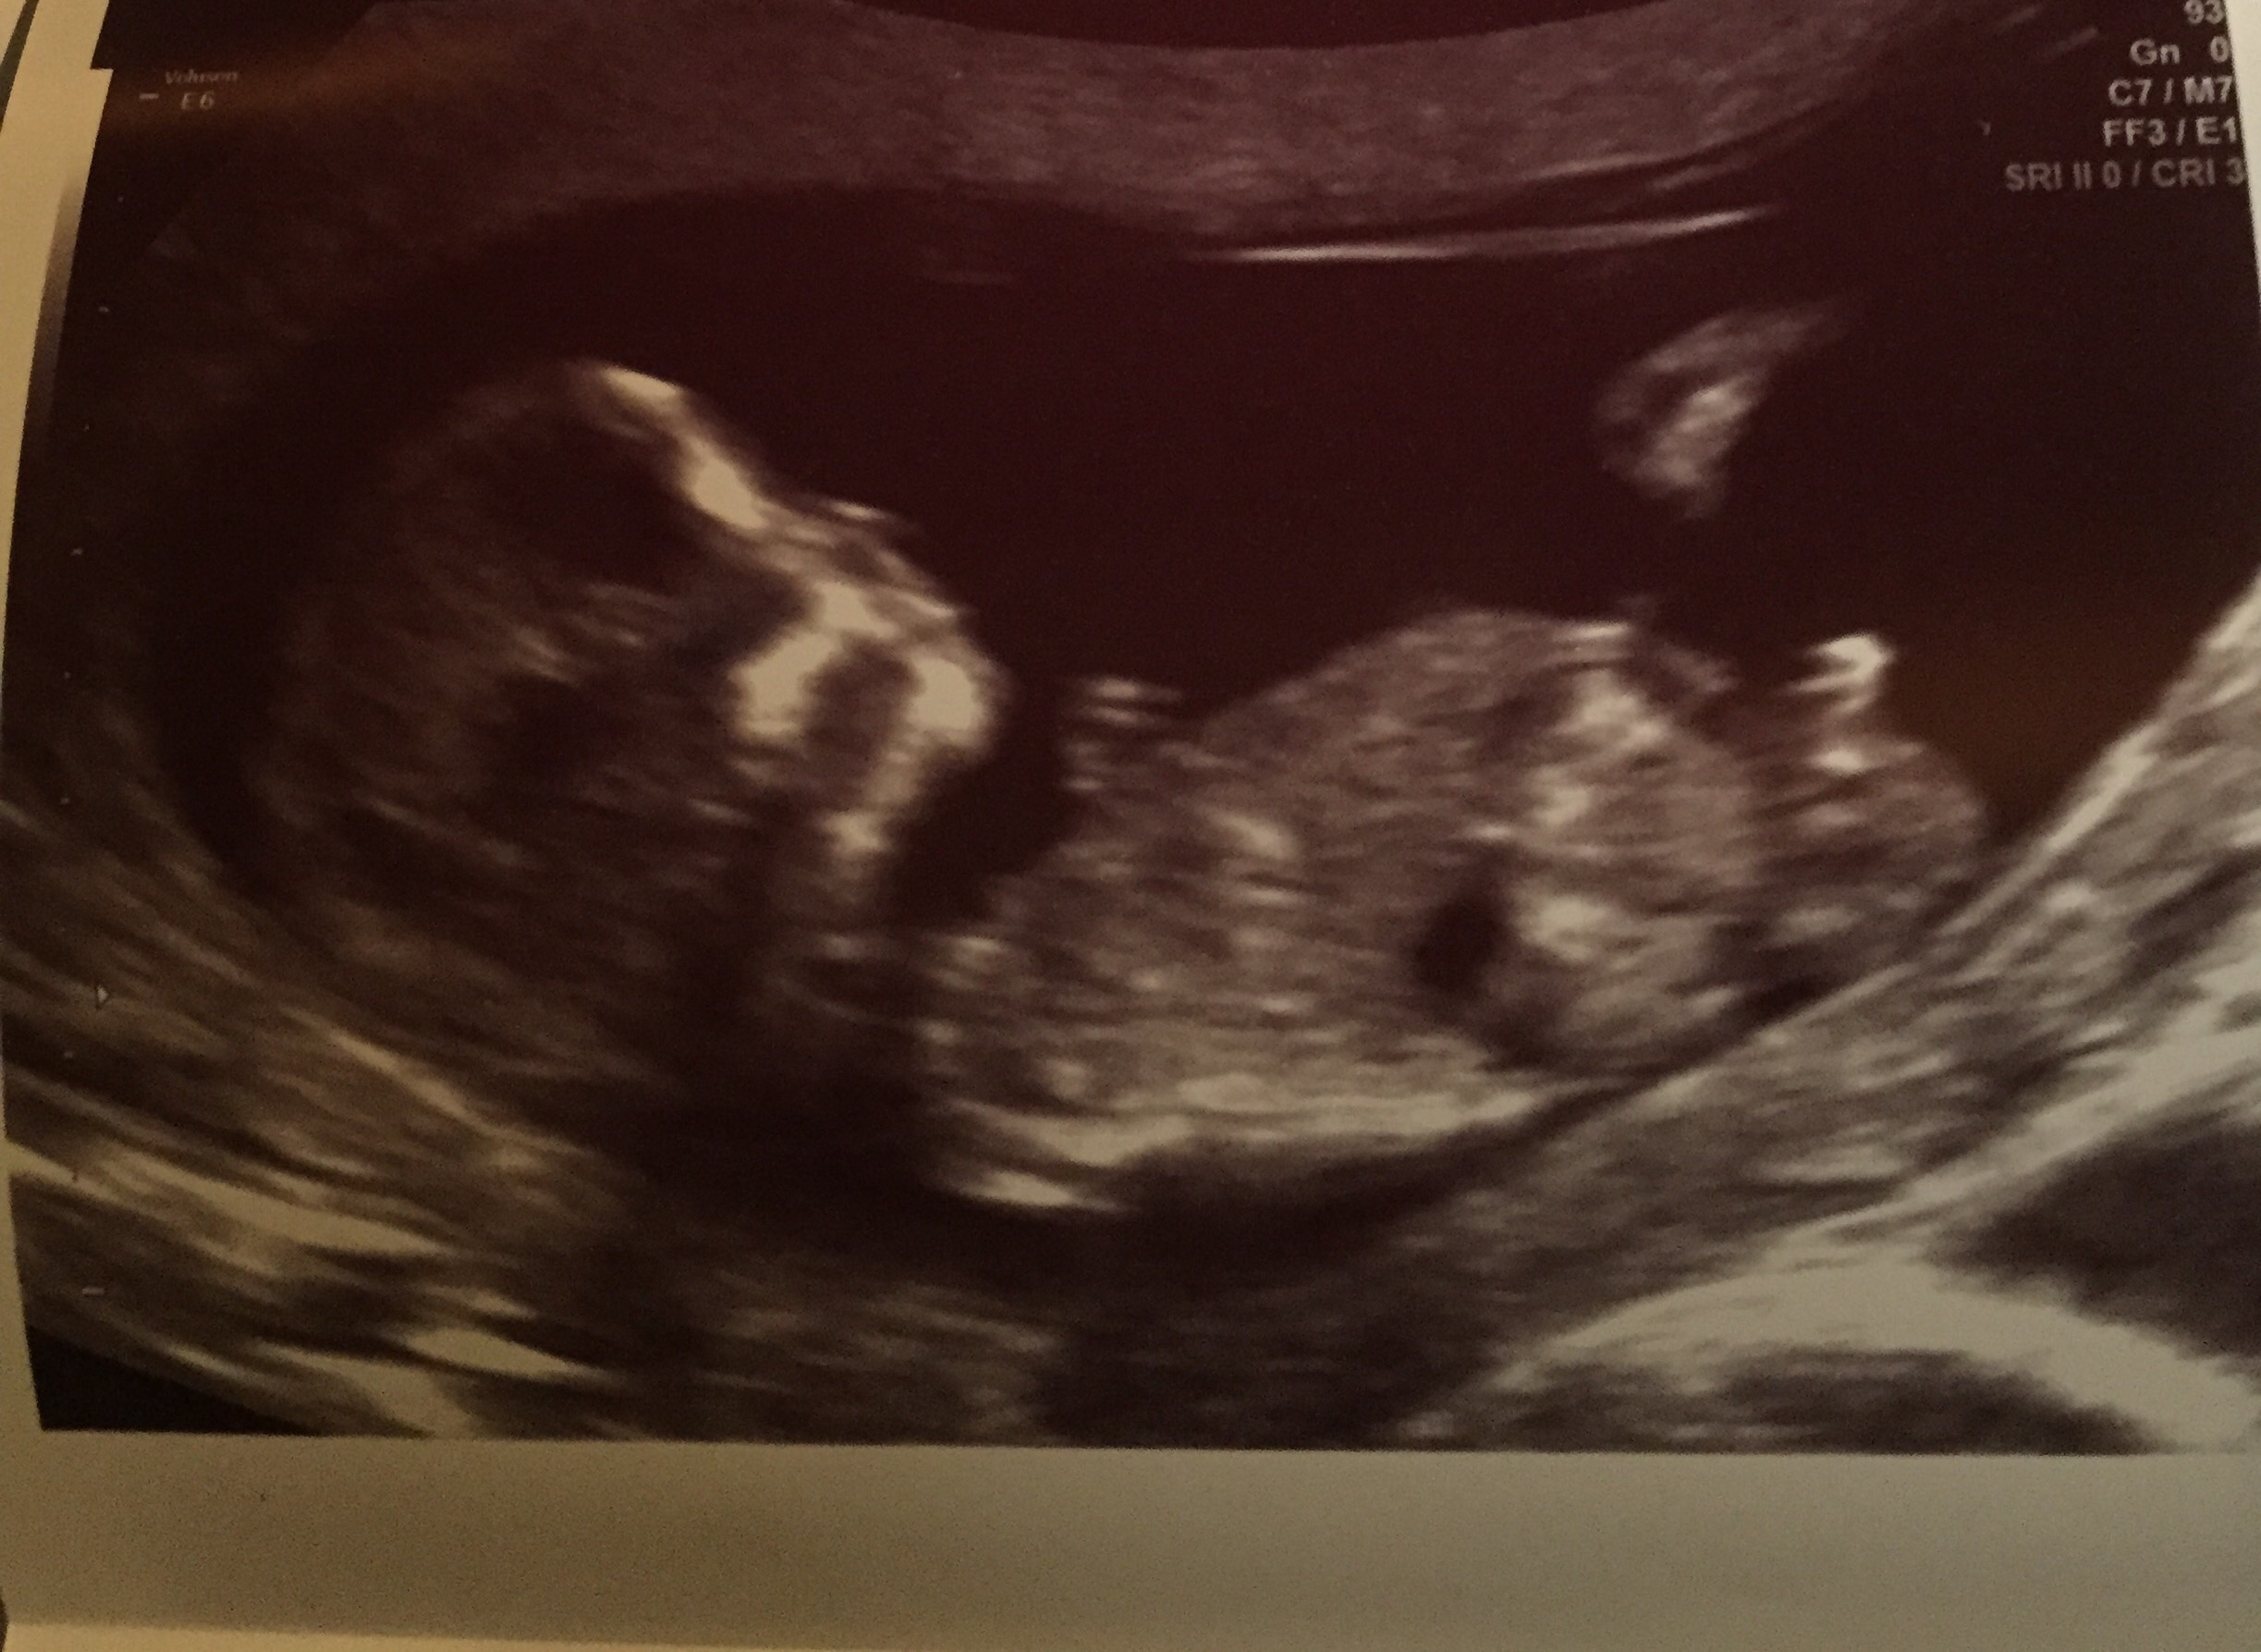

Any guesses?

Anyone?...

Boy guess on first photo but then second looks girly....